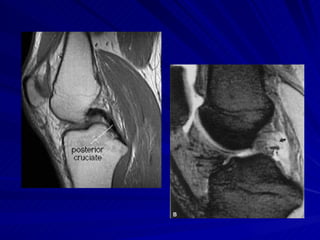

LIGAMENTOS CRUZADOS LCA – eminência intercondiliana da tíbia Porção medial do côndilo femoral lateral LCP – mais forte e mais curto Fossa intercondiliana posterior Porção lateral do côndilo femoral medial

LIGAMENTOS CRUZADOS LCA– eminência intercondiliana da tíbia Porção medial do côndilo femoral lateral LCP – mais forte e mais curto Fossa intercondiliana posterior Porção lateral do côndilo femoral medial